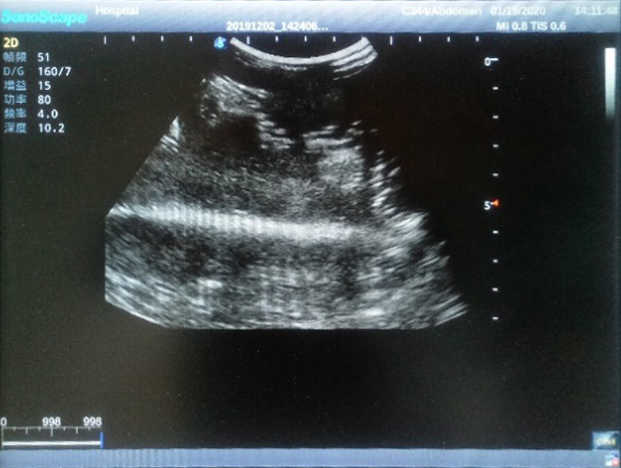

Product size(mm) 908×228×150

The Wearable Breast Ultrasound Examination Model allows users to develop and practice the skills necessary to gain proficiency in breast palpation, using ultrasound for normal and abnormal imaging and biopsy. It simulates adult female breasts with realistic size and appearance.

2)  Each model contains 8 space-occupying lesions of varying sizes, different in touch, elasticity and ultrasonogram

4) Biomimetic material allowing users to see clear and real normal tissues and space-occupying lesions that are hyperechoic, hypoechoic and isoechoic as they would see in the clinical environment